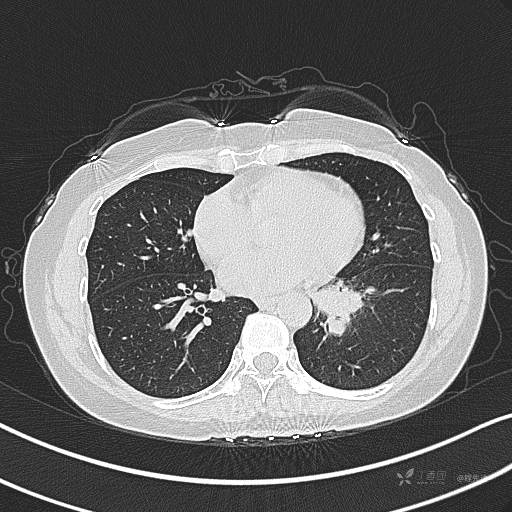

CT平扫

肺窗